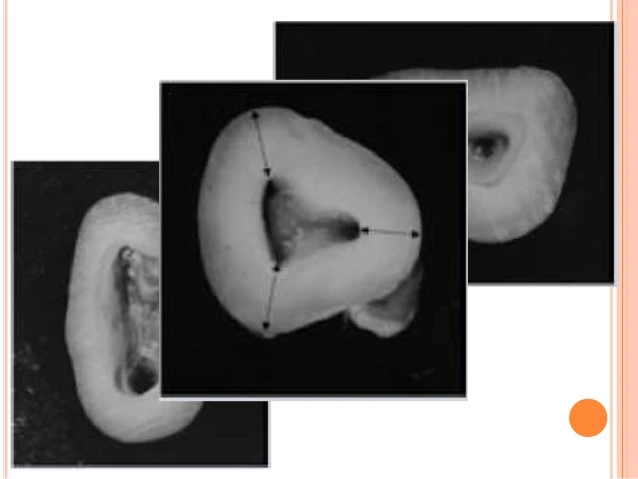

QUY LUẬT ĐỐI XỨNG

Quy luật trong điều trị nội nha : Ngoại trừ răng hàm lớn hàm trên

– Quy luật 1: “Lỗ tủy chân răng cách đều đường vẽ theo hướng gần – xa xuyên qua tâm sàn tủy”.

– Quy luật 2: “Lỗ tủy chân răng nằm trên đường vuông góc với đường vẽ theo hướng gần – xa xuyên qua tâm sàn tủy”